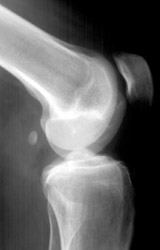

• Also known as "fender" or "bumper" fractures, tibial plateau fractures most often are the result of a moving vehicle striking the knee.

• Plateau fractures (medial and lateral) are the most common fracture sustained at the proximal tibia.

• When depression is not present, fracture may be difficult to recognize with standard radiographic exam. Alternative views and/or CT may be required for diagnosis.

• Associated damage to the anterior cruciate ligament, medial collateral ligament and medial meniscus is common due to valgus stress placed on the knee during injury.

• Postraumatic arthritis and malunion can result.